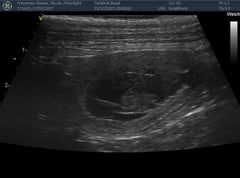

Nachdem die Geburt nicht voranschritt, entschlossen wir uns am Freitagabend 21.1.22 in die Klinik zu fahren. Nach einem Ultraschall war klar, es gibt einen Kaiserschnitt, der Uterus war gerissen und ein Welpli befand sich schon im Bauchraum. Alle Welpli waren fit mit tollen Geburtsgewichten zwischen 420 und 500g. Nachts um 2 Uhr fuhren wir nach Hause, die Welpli tranken schön bei Moon und alles sah gut aus. Aber Moon ging es am Morgen zusehends schlechter, sie bekam Fieber und war apathisch. Wieder in die Klinik, sie wurde stabilisiert und später wegen hohem Blutverlust nochmals operiert. Ein grosses Dankeschön der Tierklinik Basel, die uns übers Wochenende rund um die Uhr perfekt betreut haben und danke Melanie und Kuba fürs Blut spenden!